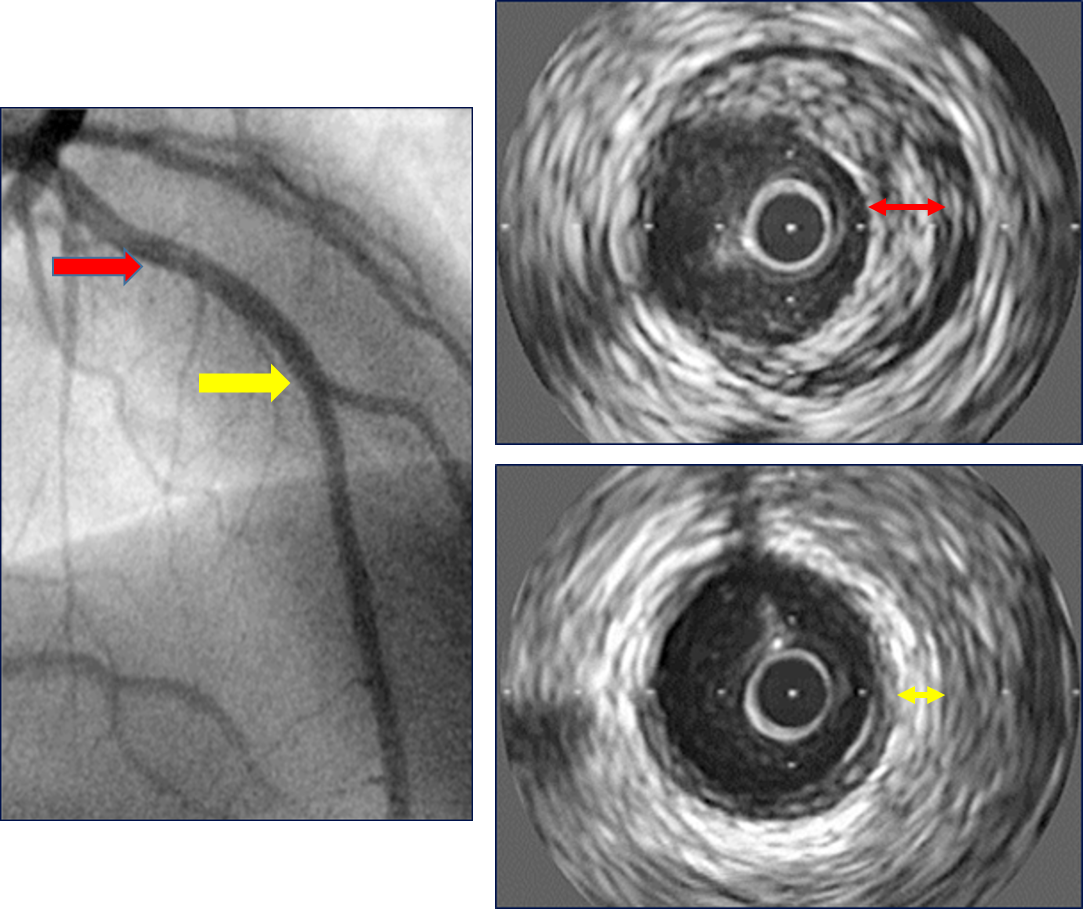

Chronic rejection: Coronary Artery Vasculopathy (CAV)

- In contrast with eccentric lesions seen in atheromatous disease, CAV results a generalized process from neointimal proliferation

- Characterized by concentric narrowing that affects the entire length of the coronary tree, from the epicardial to the intramyocardial segments, leading to rapid tapering, pruning, and obliteration of third-order branch vessels.

Intravascular Ultrasound (IVUS) is more sensitive tool for the diagnosis of CAV than coronarography (See Image below); others as MRI and Optical coherence tomography are still not widespread application in pediatrics but it is related with early diagnosis and allows changes in the treatment